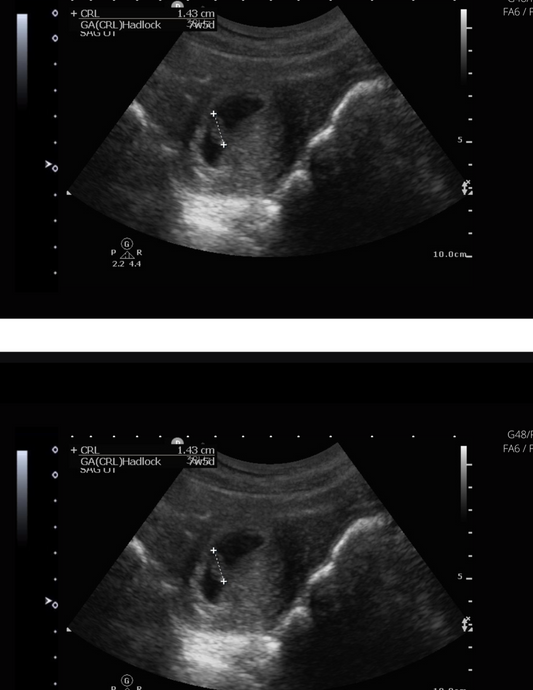

7 Weeks Pregnant Ultrasound: Your Baby's Progre...

In this blog post, we'll explore what to expect during your 7-week ultrasound and answer some common questions to keep you informed and reassured.